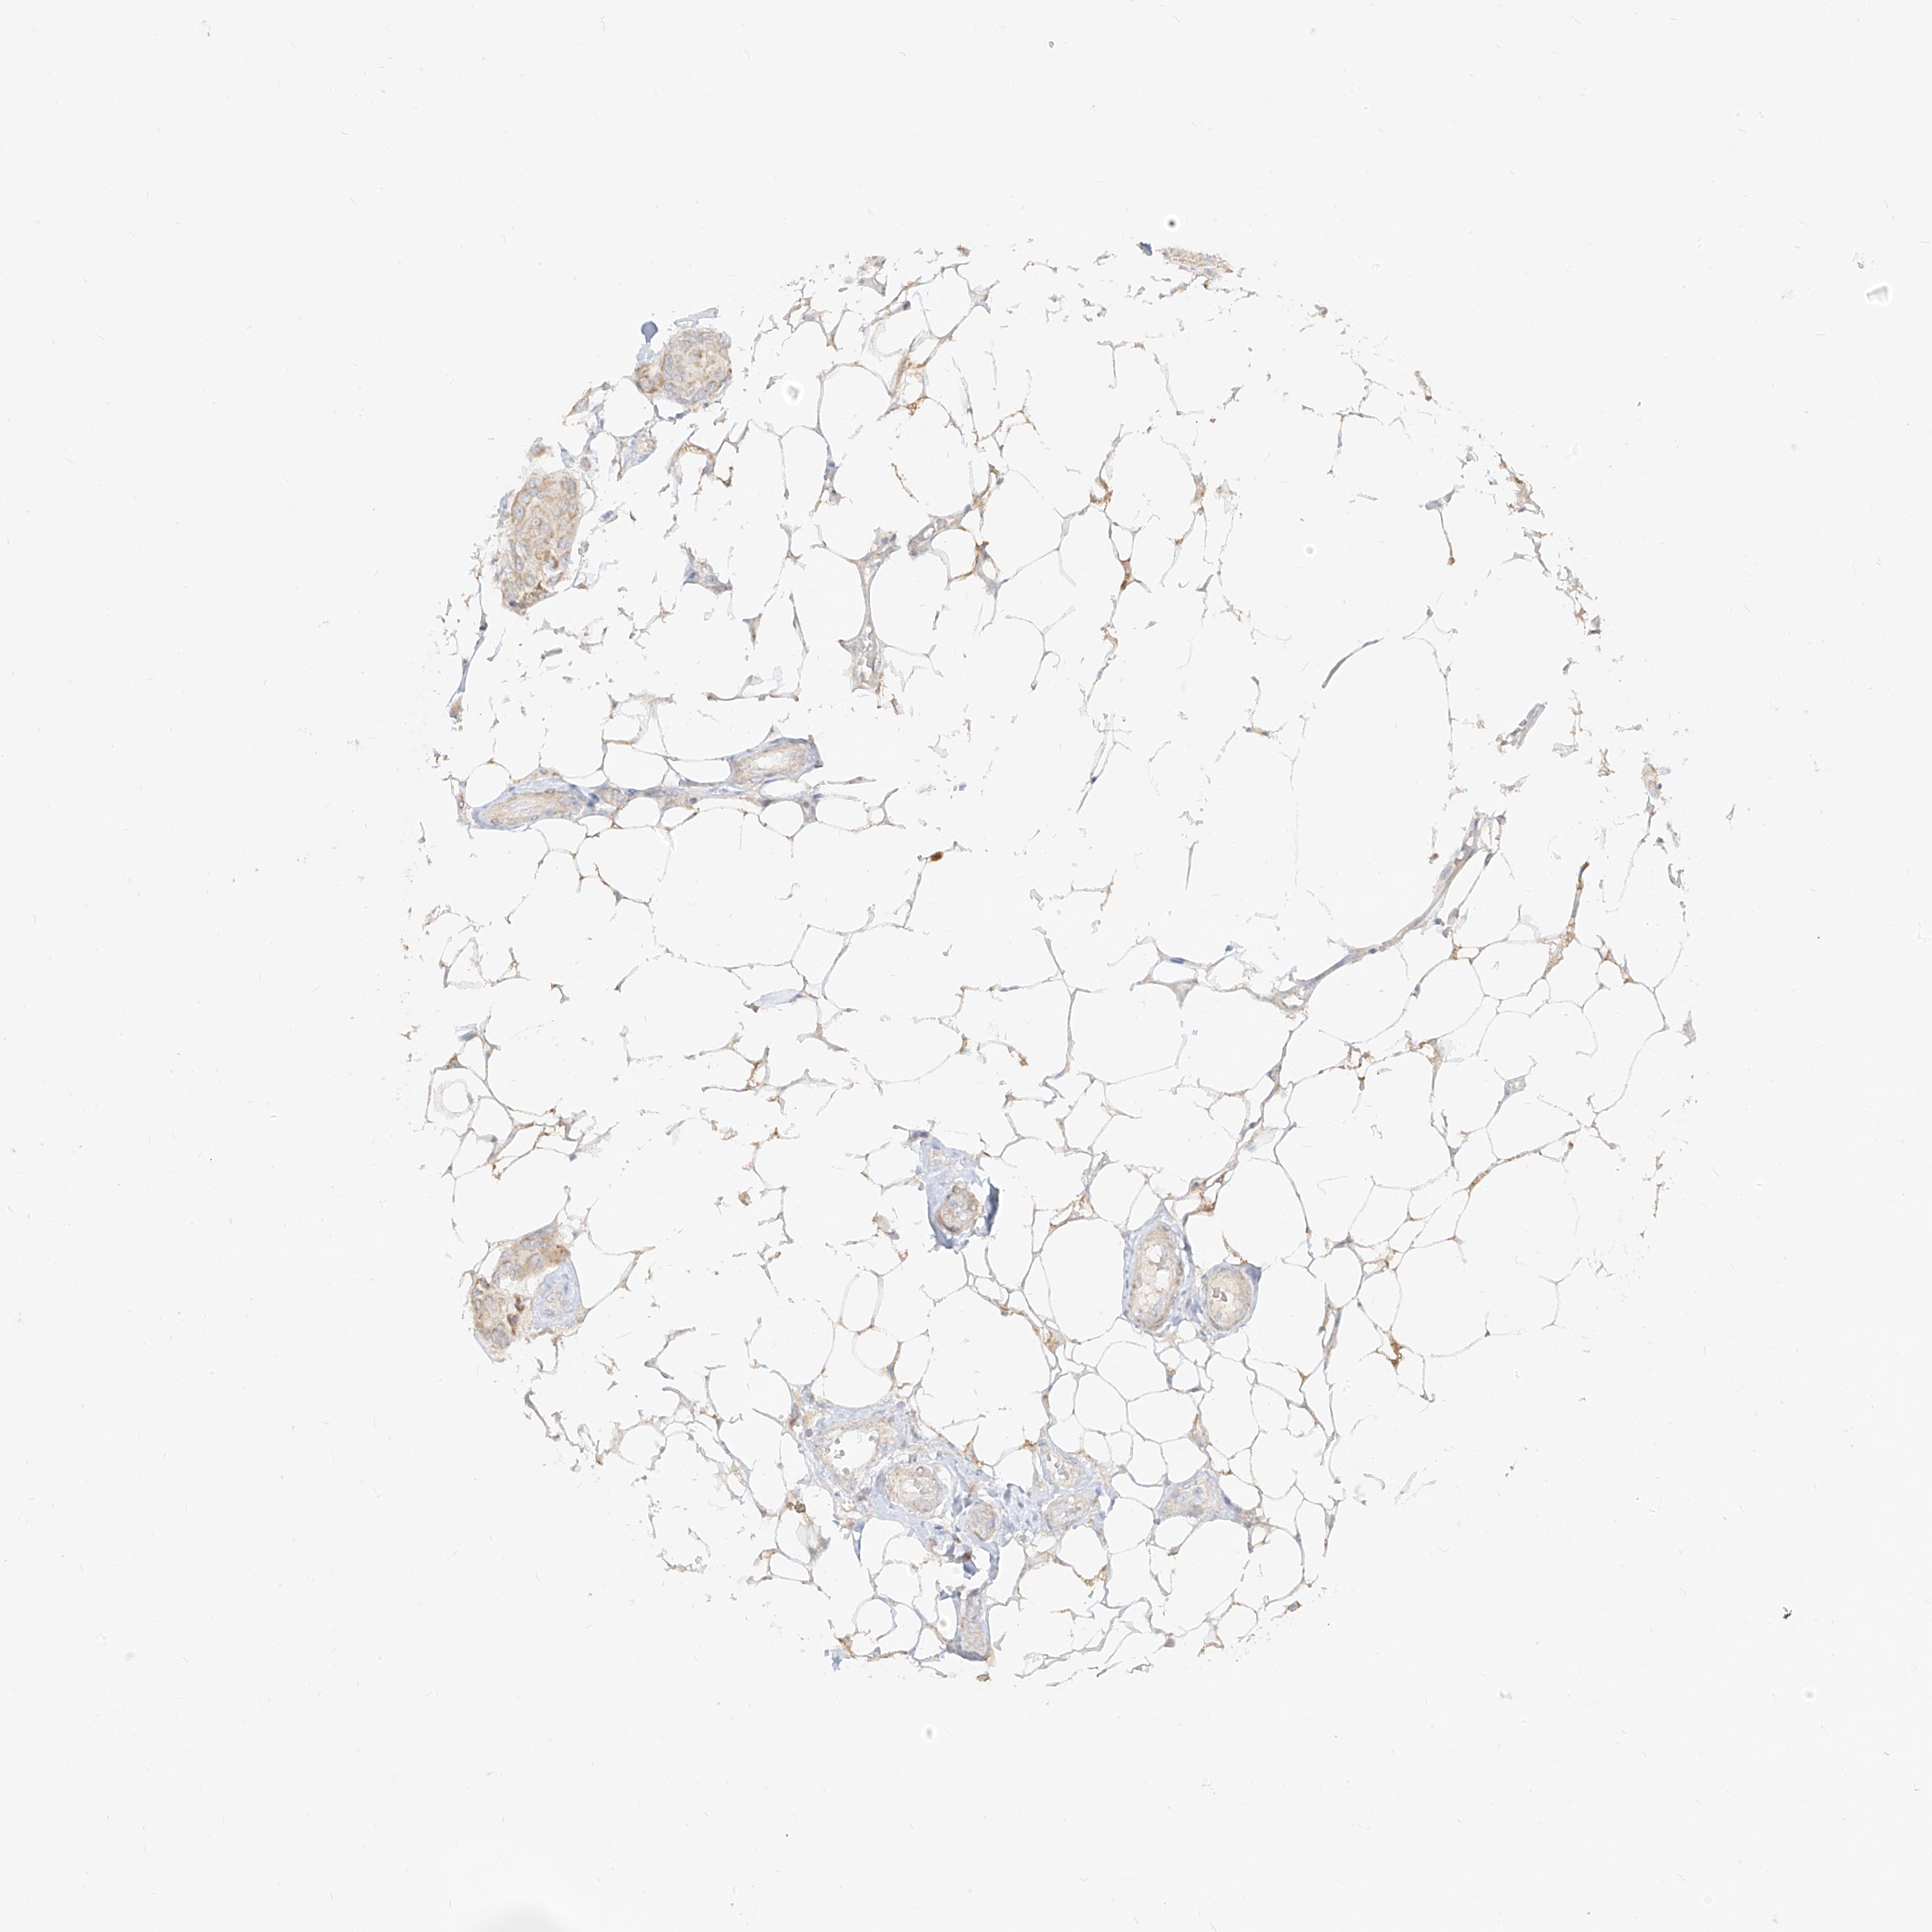

CANCER BREAST CANCER Show tissue menu

BRCA TCGA BRCA VALIDATION PROTEIN EXPRESSION

Breast cancer

Human cancer

Breast invasive carcinoma